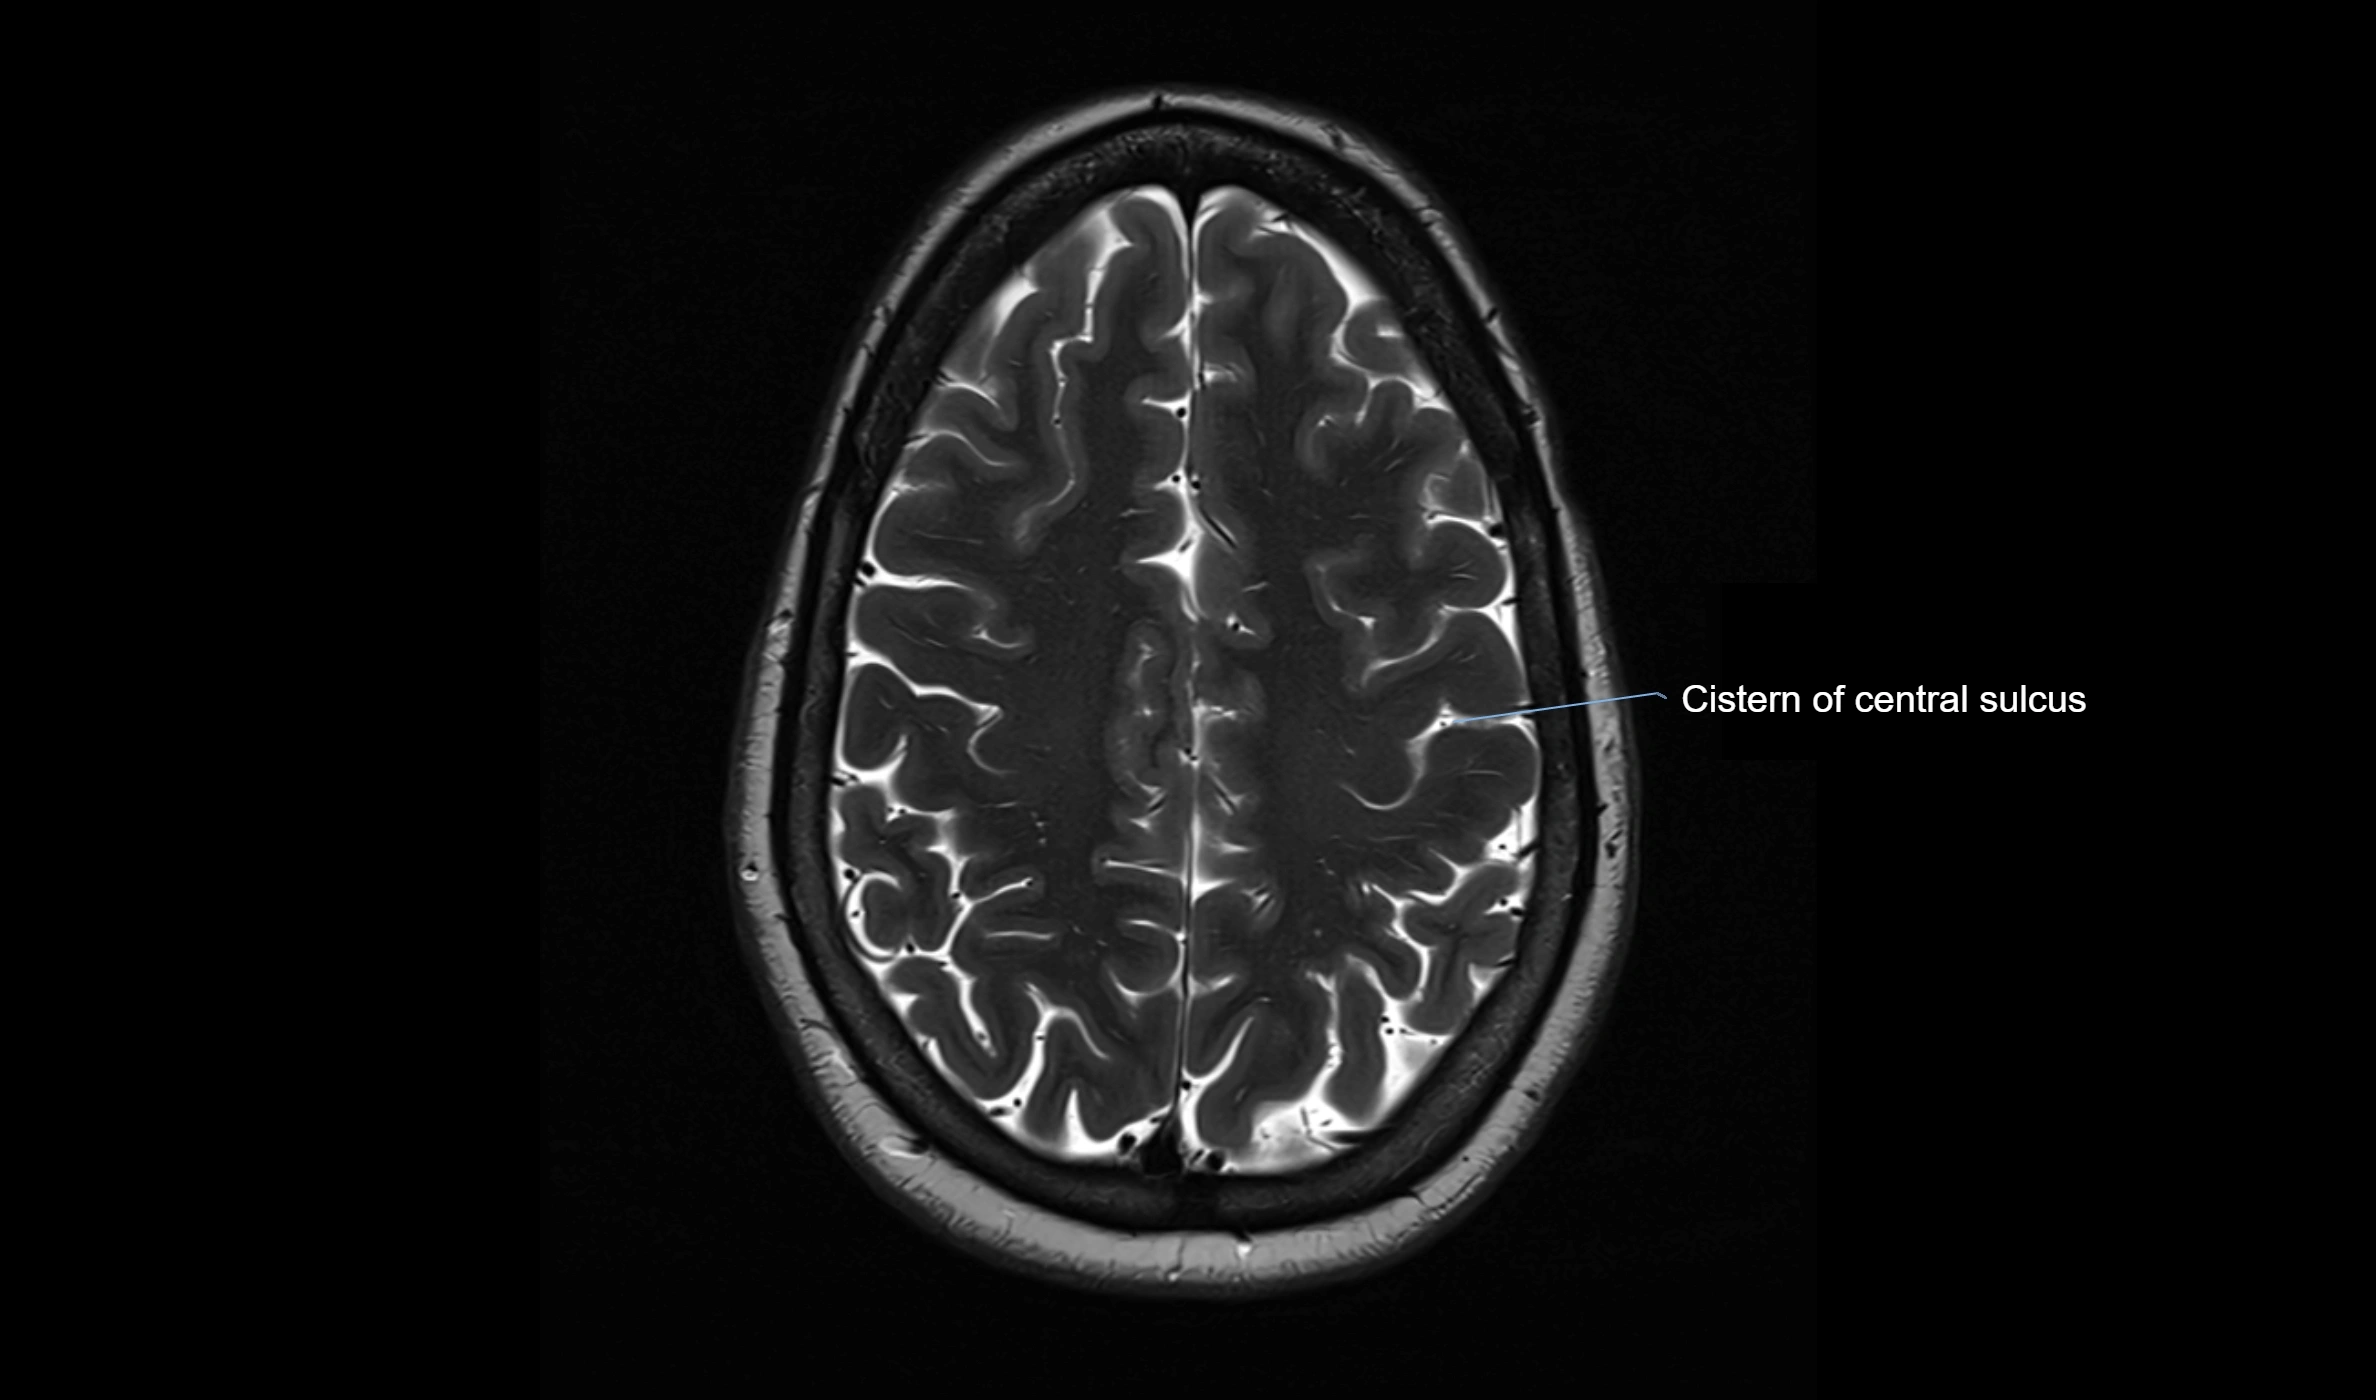

MRI images

image